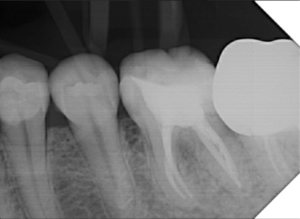

Alguns trabalhos